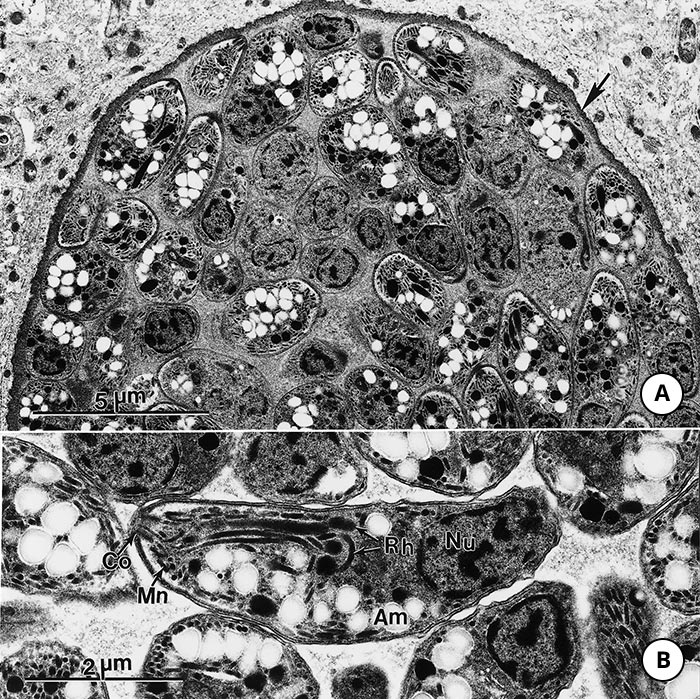

The tachyzoite is often crescent-shaped and is approximately 2 × 6 μm in size in tissue smears (Figure 2 A) and globular to oval in sections (Figure 2 B). Its anterior (conoidal) end is pointed and its posterior end is round. It has a pellicle (outer covering), a conoid, rhoptries, micronemes, a well-defined nucleus in the central area of the cell (Figure 3) and other organelles found in coccidian merozoites.28, 45

The tachyzoite enters a host cell in a variety of organs and tissues by active penetration of the cell membrane. After entering the cell the tachyzoite becomes surrounded by a parasitophorous vacuole (Figure 3) Numerous intravacuolar tubules connect the parasitophorous vacuolar membrane to the parasite pellicle (Figure 3) The tachyzoite multiplies asexually within the host cell by repeated endodyogeny. Endodyogeny (endo = inside, dyo = two, geny = progeny) is a specialized form of reproduction in which two progeny form within the parent parasite, thereby consuming it (Figure 3) Tachyzoites continue to divide by endodyogeny until the host cell is filled with parasites,45 which is the stage associated with acute toxoplasmosis in animals and humans.

The bradyzoites are approximately 7 × 1.5 μm in size. Bradyzoites differ structurally only slightly from tachyzoites. The former have a nucleus situated towards the posterior end (Figure 5 B) whereas the nucleus in tachyzoites is more centrally located (Figure 5 B) The contents of rhoptries in bradyzoites in older tissue cysts are electron-dense (Figure 3).45 Bradyzoites contain several amylopectin granules that stain red with periodic acid-Schiff (PAS). These particles are absent in tachyzoites.

Figure 3 Transmission electron micrograph of tachyzoites of Toxoplasma gondii in a parasitophorous vacuole (Pv) of host cytoplasm in the peritoneal exudate of a mouse. Note conoid (Co), electron-lucent rhoptries (Rh), dense granules (Dg), amylopectin (Am), a centrally located nucleus (N), and the intravacuolar tubular network (tnw) in Pv. One tachyzoite is dividing into two by endodyogeny. Note conoids of the daughter organisms (arrows) are present above the parent nucleus. (Prof C. A. Speer, College of Agricultural Sciences and Natural Resources, University of Tennessee, Knoxville, and Drs D. Fritz, K. Kuehl and D. Austing, USAMRIID, Fort Deterick, Maryland, USA, are acknowledged with thanks for providing this figure and Figures 4, 5 and 8)

Figure 4 Transmission electron micrograph of a young tissue cyst in a mouse brain. Note well-developed cyst wall (arrow) enclosing four bradyzoites. Note conoid (C) and posteriorly located nucleus (N) in one bradyzoite. (This figure was provided by Prof. C.A. Speer and Drs D. Fritz, K. Kuehl and D. Austing; vide Figure 3)

Figure 5 Transmission electron micrograph of a large tissue cyst of Toxoplasma gondii in a mouse brain.

- Note thin cyst wall (arrow) and many bradyzoites

- Higher magnification of a bradyzoite in longitudinal section.

Note conoid (Co), micronemes (Mn), electron-dense rhoptries (Rh) with convoluted necks, and a terminally located nucleus (Nu). (This figure was provided by Prof. C.A. Speer and Drs D. Fritz, K. Kuehl and D. Austing; vide Figure 3)